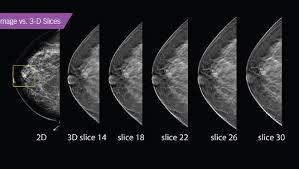

Essentially, mammograms turn a 3d object into a 2d object. This is why you should always talk to your doctor if you notice an unexplained change in the size of a breast. What does the doctor look for on a mammogram? cancer.org. A screening mammogram is performed at regular intervals to check for breast cancer in women who have no signs or symptoms of the disease. Bright spots on a mammogram that look like potential tumors could turn out to be overlapping tissues or a blood vessel folding over on itself, friedewald said. To license this video for patient education or content marketing, visit: What does breast cancer look like? This overlapping tissue can cause the resulting image to look like cancer. Finding breast lumps and seeing change in the size and shape. Screening mammograms have been used since the 1980s. Digital breast tomosynthesis (tomo), also known as 3d mammography, is a revolutionary new screening and diagnostic breast imaging tool to improve the early detection of breast cancer. Ultrasound characterization of breast masses. indian journal of radiology and imaging. Calcifications are calcium deposits within the breast tissue and they look like small white spots.

Automatic Breast Ultrasound State Of The Art And Future Perspectives Ecancer from ecancer.org It appears to be developing in a concentric pattern. The tumor cells don't stay within the clear borders of the mass, but instead invade the nearby breast tissue. Normal breast tissue can look 100,000 different ways on a mammogram. A screening mammogram is performed at regular intervals to check for breast cancer in women who have no signs or symptoms of the disease. This includes mammography, ultrasound and breast mri. Diagnostic mammograms involve taking more views than screening mammograms. However, 3d allows us to 'slice through' the breast, making thin sections, like on a ct scan. It's so important to listen to the messages our bodies are telling.

Moose & doc breast cancer, 21 may 2018. We'll show you breast cancer pictures to help you identify any physical traits of the condition. Normal breast tissue can look 100,000 different ways on a mammogram. Finding breast lumps and seeing change in the size and shape. Dense breast tissue appears solid. Essentially, mammograms turn a 3d object into a 2d object. American cancer society, 9 oct 2017. That makes it easy to detect abnormalities, which generally show up as white. A 3d mammogram is used to look for breast cancer in people who have no signs or symptoms. More importantly, the overlap can obscure small breast cancers. A screening mammogram is performed at regular intervals to check for breast cancer in women who have no signs or symptoms of the disease. Several patterns of calcifications are seen with dcis, including: Breast cancer and some noncancerous (benign) breast conditions can appear white on a mammogram.

Breast cancer and some noncancerous (benign) breast conditions can appear white on a mammogram. This overlapping tissue can cause the resulting image to look like cancer. Diagnostic mammograms involve taking more views than screening mammograms. It's so important to listen to the messages our bodies are telling. A number of studies have found that 3d mammograms find more cancers than traditional 2d mammograms and also reduce the number of false positives. Ultrasound characterization of breast masses. indian journal of radiology and imaging. Even if you have a lump in only one breast, pictures will be taken of both breasts. Finding breast lumps and seeing change in the size and shape. 1 the gray areas correspond to normal fatty tissue, while the white areas are normal breast tissue with ducts and lobes. A false positive is when a mammogram shows an abnormal area that looks like a cancer but turns out to be normal. Breast cancer can appear as a spiculated mass, cluster of tiny calcifications, smoothly marginated mass, area of subtle distortion or be invisible on. Macrocalcifications, which look like small white dots on a mammogram. One advantage of ultrasound technology is that it allows substantial freedom in obtaining breast images from any orientation.